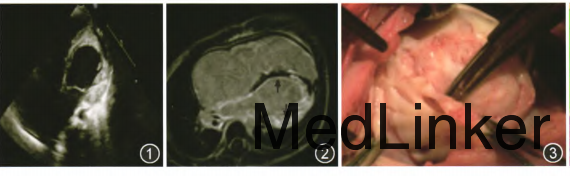

查体:呼吸50次/min,心率130次/min,颜面浮肿,颈静脉怒张,肝颈静脉征阳性。肝右肋平脐,质中。心音低钝,未闻及明显杂音。 辅助检查:多次血常规检查嗜酸性粒细胞总数(0.01~0.49)×109/L,在正常范围。(CK-MB)16~80 U/L,(cTnl)0.17~4.48 μg/L,(BNP)653~8022 ng/L,三项指标均呈进行性增高。心电图示不完全性右束支传导阻滞。胸x线片示心脏明显增大,心胸比例0.68,双肺有渗出,左侧少量胸腔积液。超声心动图检查示左心室心尖部闭塞,室间隔反射增强,内膜厚约11 mm,左心室后壁厚约13.6 mm。三尖瓣中至重度反流,卵圆孔右向左分流。 左心室舒张末径(LVDd)30mm,左心室射血分数(LVEF)48%,二尖瓣E峰、A峰倒置,E/A<1,组织多普勒二尖瓣环室间隔组织流速:S'3 cm/s,E’4 cm/s,A’6 cm/s。MRI示右心房及左右心室增大,左右心室心肌壁增厚,最厚处21mm,黑血序列见心肌内信号较弥漫性增高,延迟扫描见左心室心内膜、游离壁及后壁异常强化影,与正常心室肌分界不清,右心室心内膜少许条带状异常强化影,符合心内膜心肌纤维化(EMF)改变,LVEF22.4%,右心室射血分数(RVEF)22.8%,运动功能评估左、右心室各室壁运动功能减低,卵圆孔未闭,二尖瓣轻度反流,三尖瓣中至重度反流。

诊断:EMF,双室型,心室收缩、舒张功能减退。 治疗:在全身麻醉和体外循环下行心内膜纤维剥离、三尖瓣成形、双向Glenn术。术中见全心扩大,心内膜广泛纤维化,三尖瓣对合不佳,重度反流。切取心内膜组织标本送病理检查并弹力染色、Masson染色,见心内膜下胶原纤维增生,侵及心肌使心内膜下心肌呈岛屿样分布于纤维中,符合EMF改变。术后患儿反复出现心律失常(频发室性早搏、房颤、阵发性室上性心动过速),严重感染以及难以控制的心力衰竭,并出现肝肾功能衰竭,最终家长放弃治疗,于术后22d死亡。